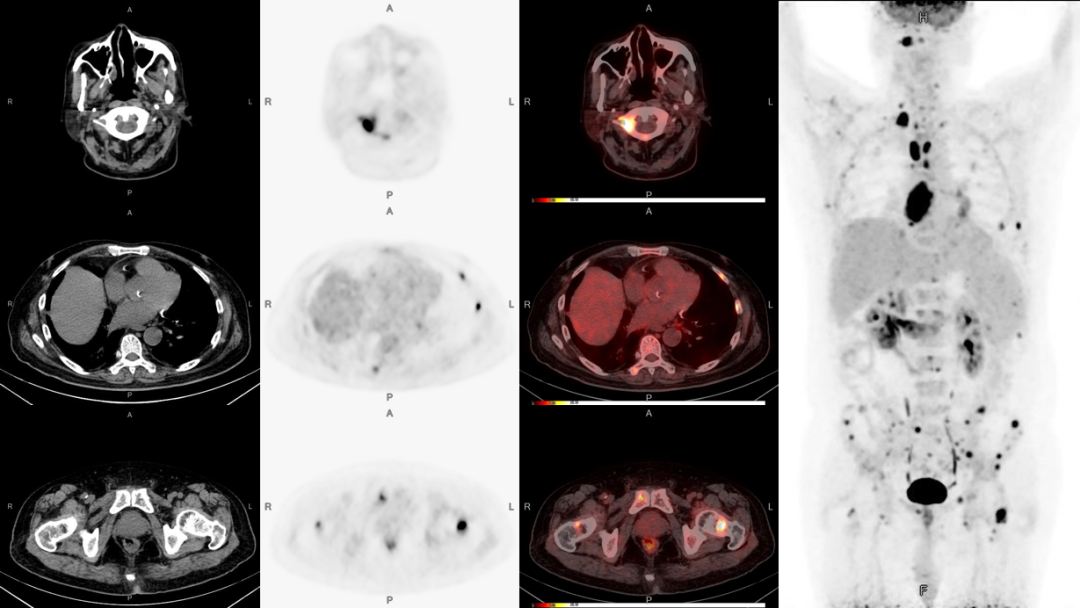

病例2:男性,51歲,反復(fù)咳嗽無(wú)痰半年余;發(fā)現(xiàn)左側(cè)鎖骨內(nèi)腫塊數(shù)月余。

3、雙股骨上段轉(zhuǎn)移可能。